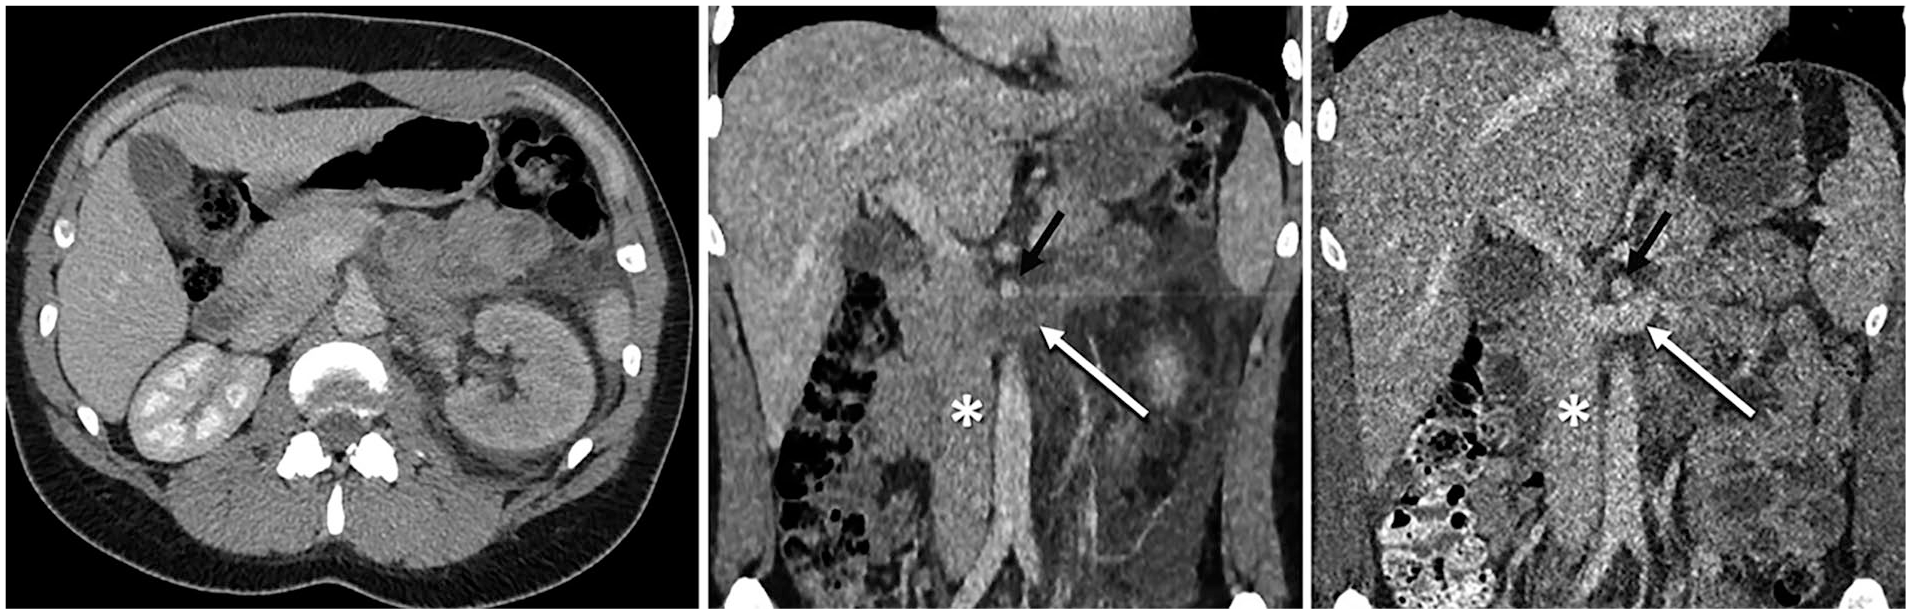

Venous phase computed tomography (CT) angiographies. Pre-operatively (left and center), the left kidney was poorly opacified and oedematous with perirenal fat stranding and total obstruction of the renal vein (white arrow). Post-operatively (right), the left renal vein is fully opacified. The inferior vena cava (*) and super mesenteric artery (black arrow) are marked.

The patient was tender in her left flank, with a urine dipstick positive for hematuria. Her white cell count was 10.7 × 109/L, CRP 91.2 mg/L, and serum creatinine 131 µmol/L. A computed tomography (CT) scan without contrast demonstrated a grossly oedematous left kidney with perirenal fat stranding and free fluid tracking along the perirenal space down to the left iliac fossa. The left renal vein was abnormally distended and hyperattenuating, suggesting left RVT. A subsequent contrast-enhanced 3-phase CT angiogram showed normal renal arteries but delayed left parenchymal enhancement and no excretion of urine (Figure 1). The distended left renal vein did not opacify, confirming the suspicion of total venous obstruction (Figure 2). The thrombus did not extend into the inferior vena cava (IVC). The right kidney was entirely normal. The patient was started on heparin infusion.